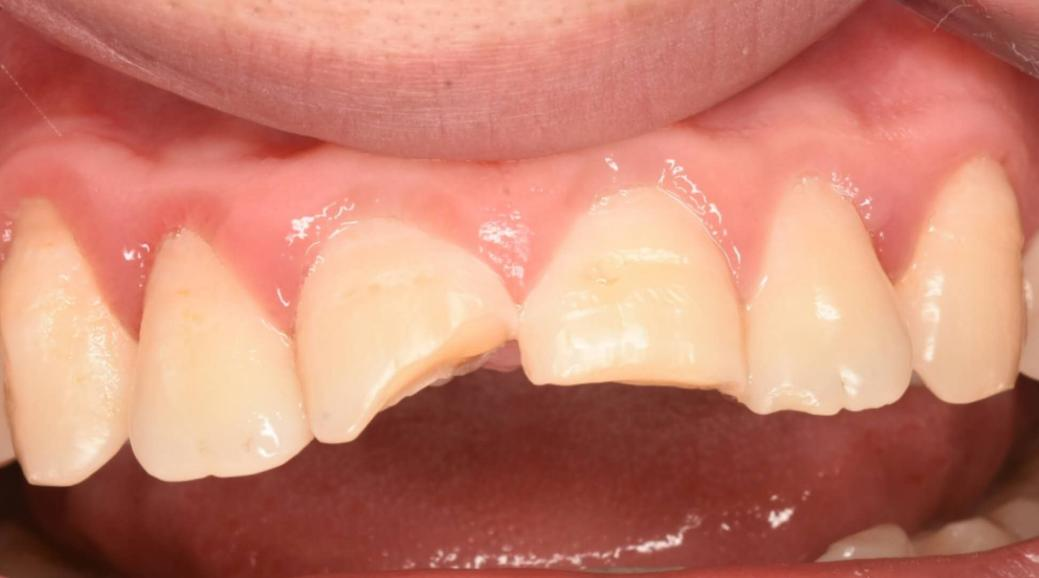

Many people don't know. In fact, when a tooth is broken, ultra-thin porcelain veneers or micro-veneers can be selected for restoration depending on the severity of the situation. As long as the pulp is not damaged, the broken surface can be slightly polished and then veneer restoration can be performed. Such as the teeth like the following:

Since only the veneers of the two front teeth need to be made and there is no need to change the color, it is sufficient to compare with the abutment color.